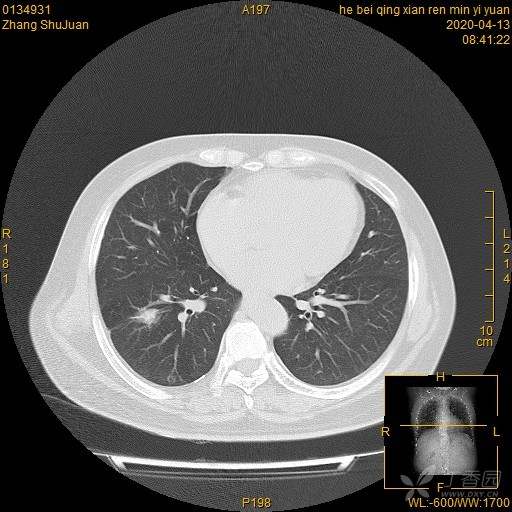

西门开心 +5 丁当患者性别:女

患者年龄:49

简要病史:体检发现右肺结节,不吸烟。

体格检查:无阳性体征

辅助检查:血常规、血沉正常,血肿瘤标志物正常。FET-CT倾向恶性结节

临床诊断:右肺结节

治疗经过:手术

大家猜猜病理是什么?